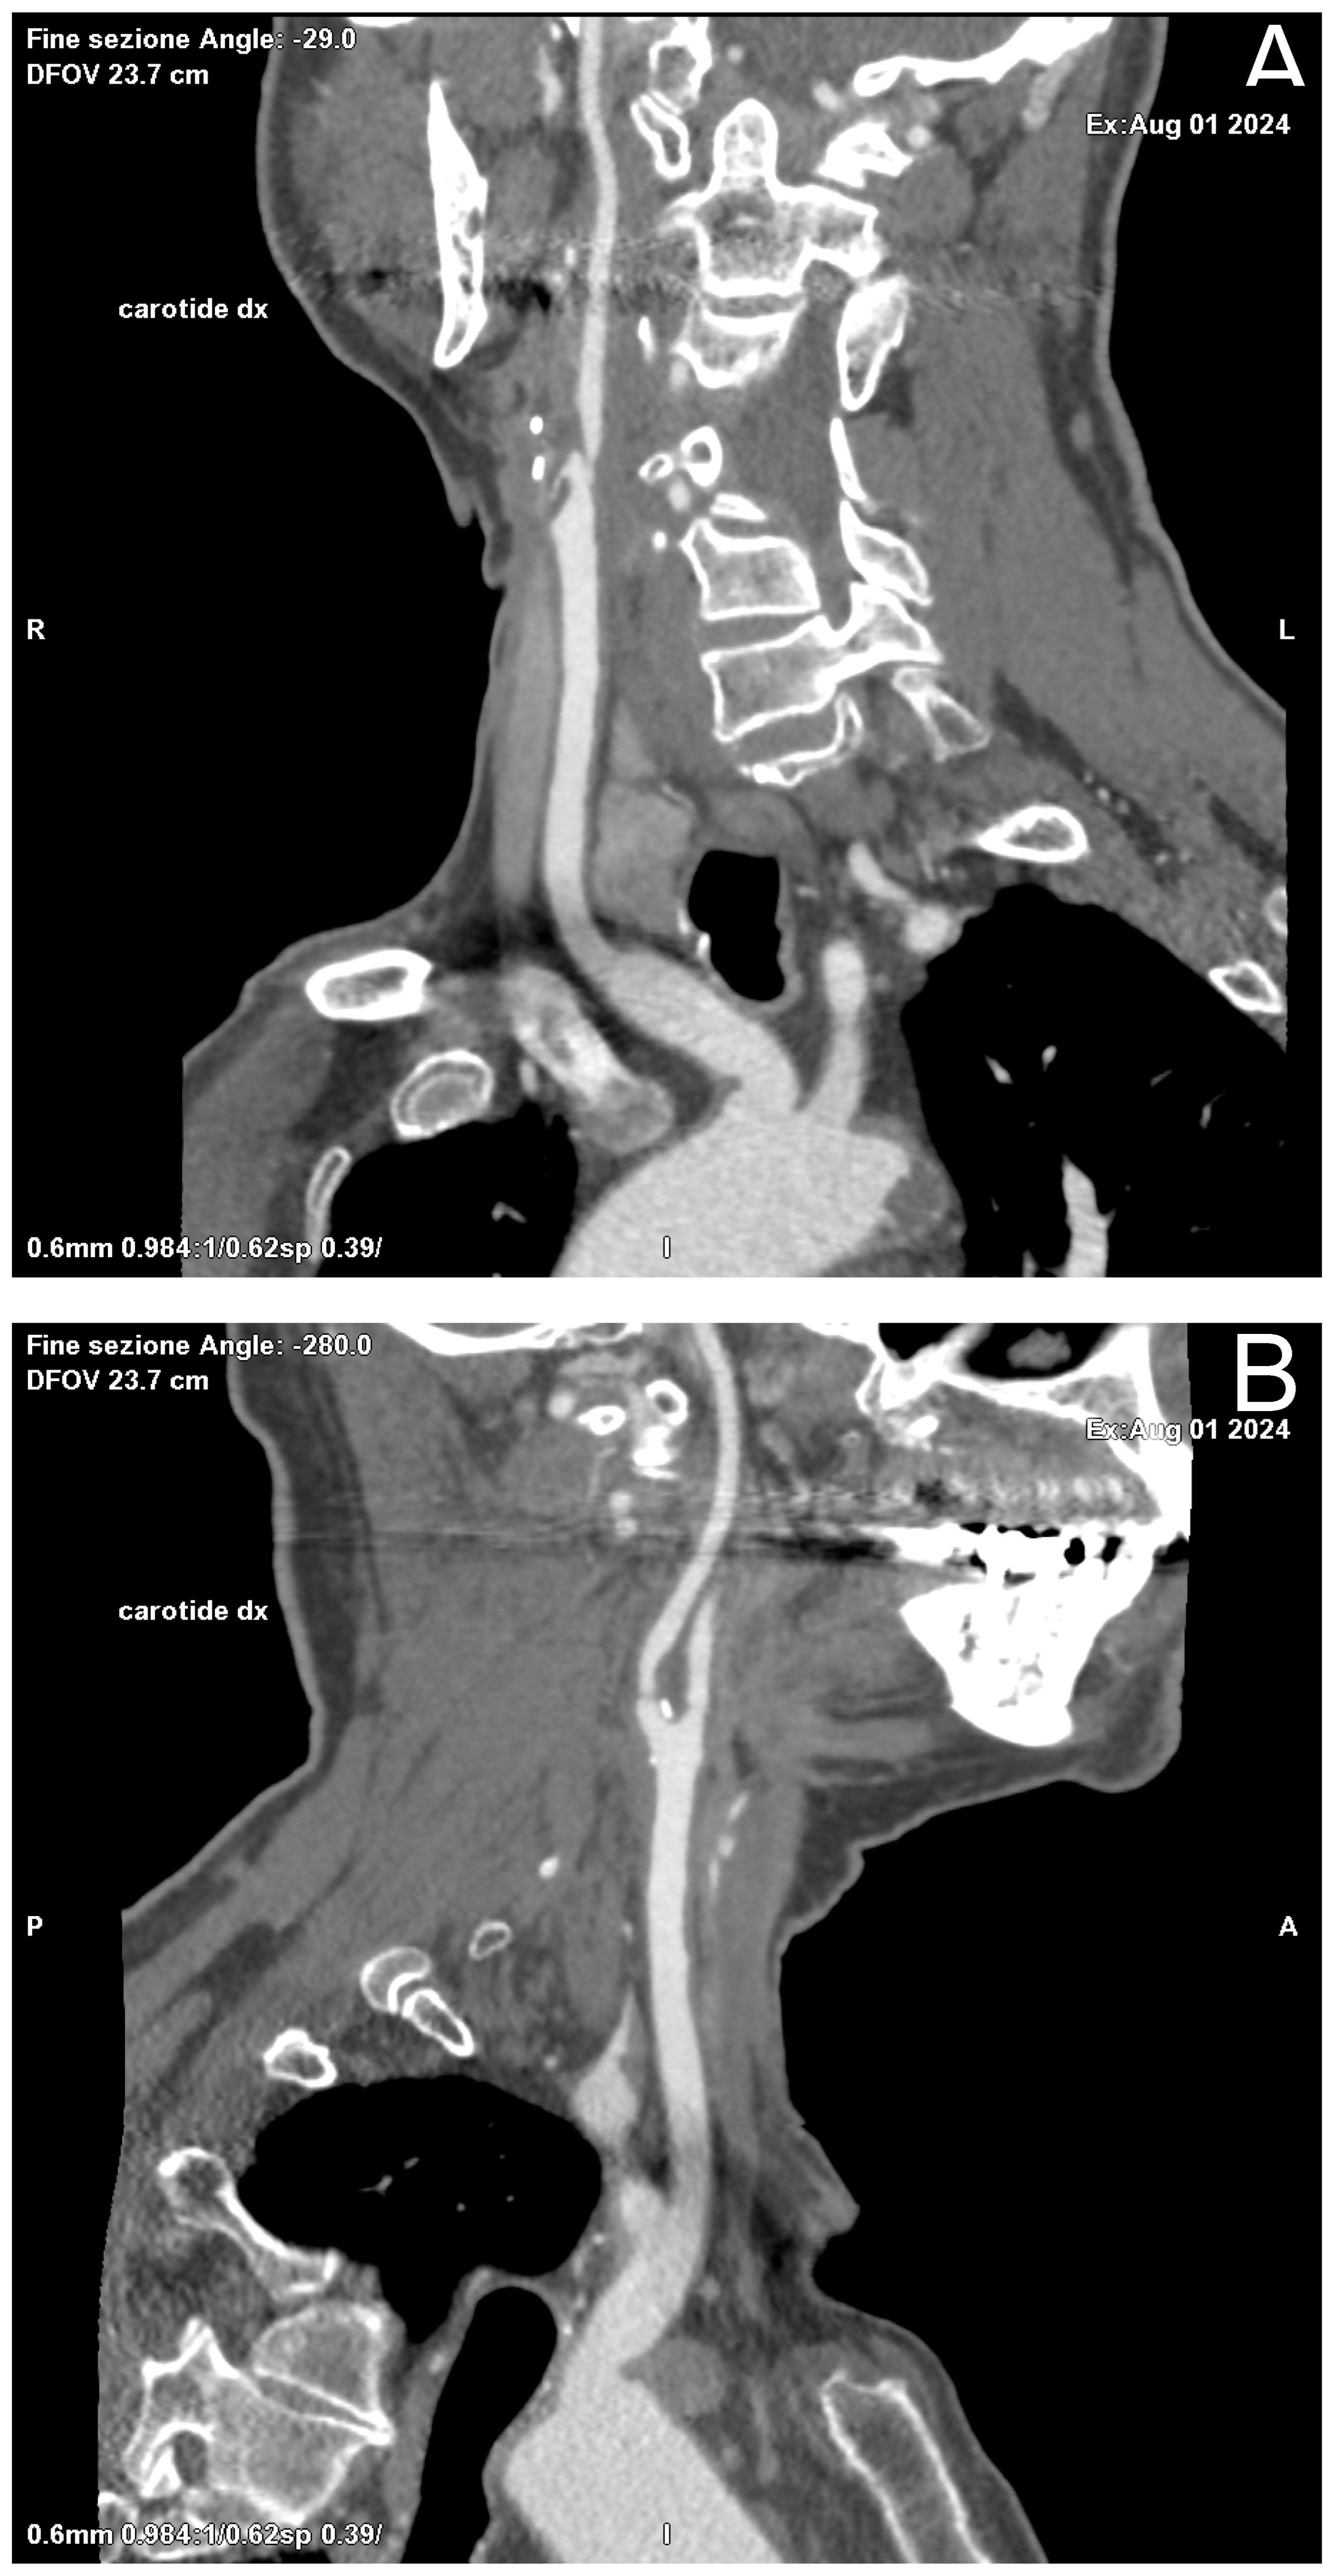

Figure 2. Oblique Coronal (A) and Sagittal (B) reformation performed for preoperative planning, which shows a mixed component plaque, determining stenosis of at least 50% in the right ICA in the post-ostial tract.

Among other diagnostic tests available for the evaluation of carotid stenosis, CT is often a second-choice test, performed as an adjunct to US. CT allows a more accurate and precise assessment of both plaque morphology and the degree of stenosis and, being relatively standardized across institutions and platforms, is not affected by operator influence. In addition, by providing a panoramic view of the entire vascular circle of the head and neck district, it allows us to analyze, in a single acquisition, both carotid arteries and the intracranial arterial circle, not accessible by ultrasound; moreover, it could be used for planning revascularization therapies thanks to reformatting software like MPR (Figure 2) and Volume Rendering (VR) (Carestream, ImageView Software, version 2.1, 150 Verona Street, Rochester, NY, USA).